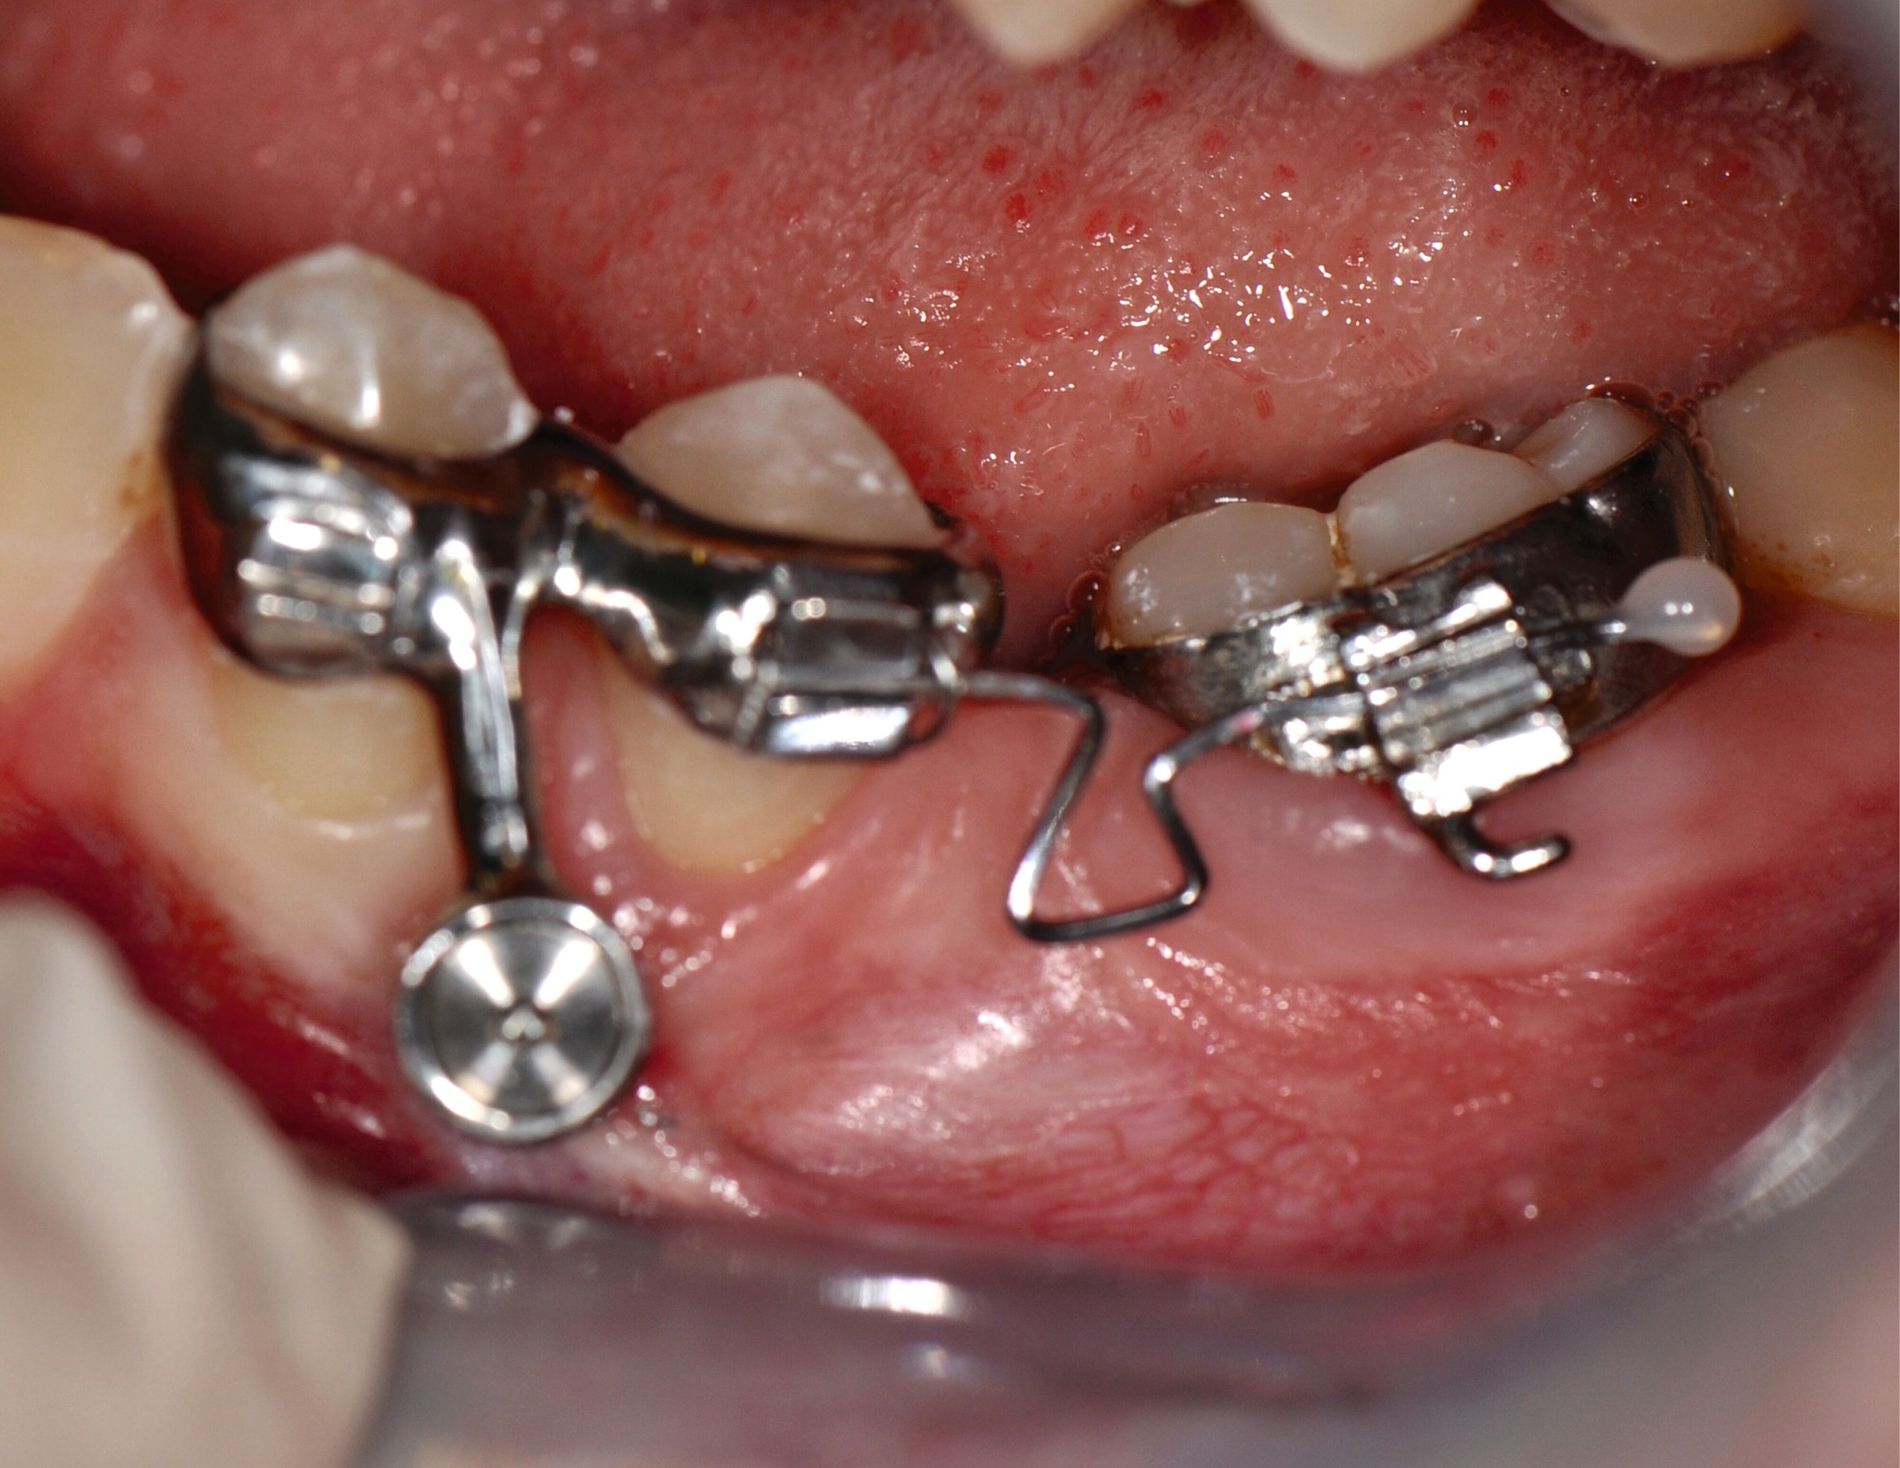

Als Alternative zu Alignern können auch Brackets mittlerweile im 3-D-Druckverfahren hergestellt werden [Sha et al., 2018; Sha et al., 2019; Bauer et al., 2023] (Abbildungen 2a und 2b). Neben der Nutzung des Angebots kommerzieller Anbieter (beispielsweise Lightforce Company) besteht dabei die Möglichkeit der Herstellung im praxisinternen 3-D-Drucker. Zum Einsatz eignen sich unter anderem Keramik-gefüllte 3-D-Druckkunststoffe der Biokompatibilitätsklasse IIa, die für einen langfristigen intraoralen Einsatz zertifiziert sind (zum Beispiel Permanent Crown Resin, Formlabs) [Papageorgiou et al., 2022; Bauer et al., 2023; Hodecker et al., 2023; Panayi, 2023].

Die Vorteile bestehen vordergründig in einem individualisierten Design, das die jeweiligen Therapieanforderungen berücksichtigt. Bisherige Forschungsarbeiten zeigen eine mit konventionellen Metallbrackets vergleichbare Präzision [Bauer et al., 2023], so dass eine korrekte Übertragung kieferorthopädischer Kräfte gewährleistet ist. Der Haftverbund zeigt sich gegenüber konventionellen Metallbrackets noch etwas schwächer [Hodecker et al., 2023]. Durch weitere Entwicklungen im Bereich der Bracketbasis dürfte diese Limitation jedoch adressiert werden können.